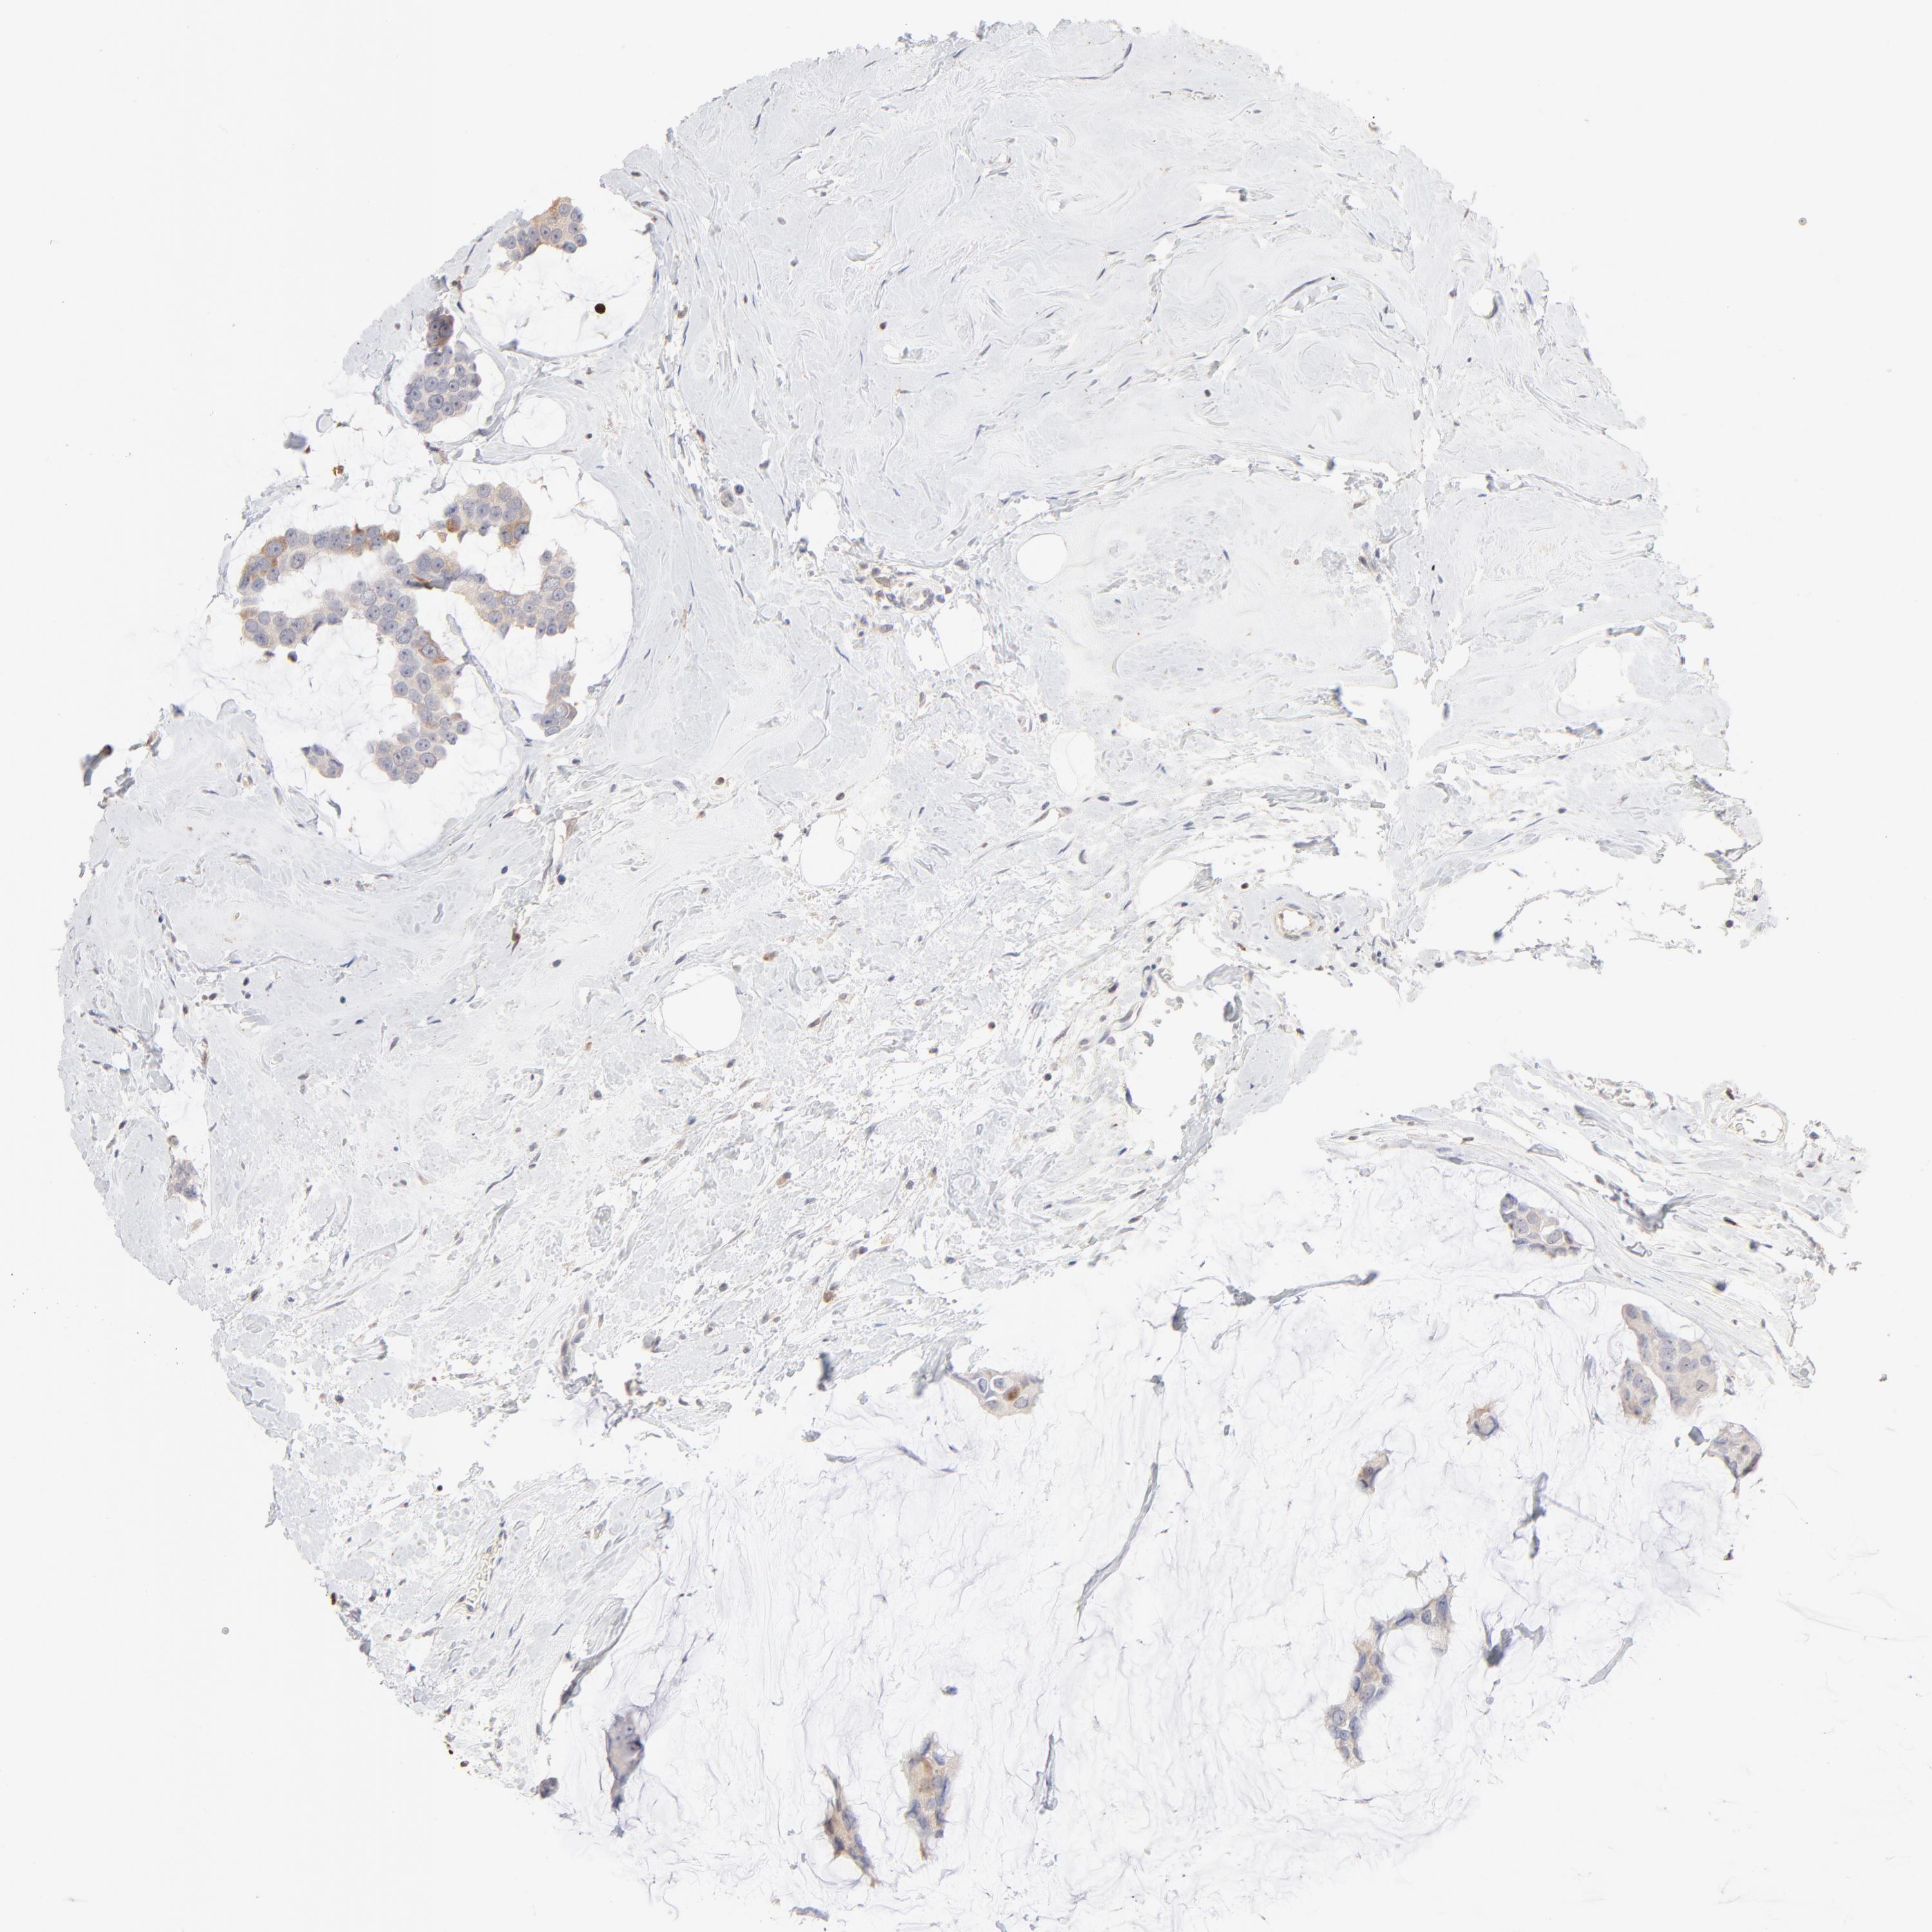

BRCA TCGA BRCA VALIDATION PROTEIN EXPRESSION

ANTIBODIES

AND

VALIDATION